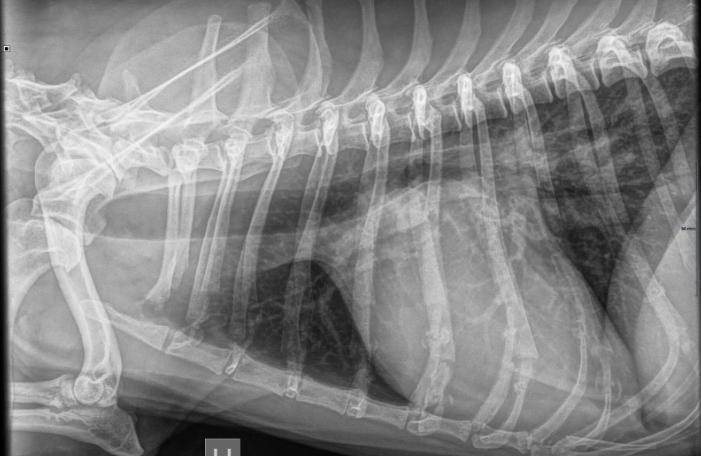

Røntgen

Røntgenundersøkelser er et nyttig hjelpemiddel i mange former for diagnostikk og utredninger.

Vi tar daglig bilder av dyr i forbindelse med:

• ledd og beinproblemer

• bukbilder ved smerter i buk eller diaréproblemer

• thorax/brystbilder i forbindelse med pusteproblemer eller hoste

• tannrøntgen ved kontroll av tenner

Andre bruksområder kan være drektighetsrøntgen for å telle antall valper, eller HD/AD-vurderinger som sendes til Norsk Kennelklubb.

Når ditt dyr skal til en røntgenundersøkelse er det en fordel om dyret er fastet på forhånd.

Noen ganger krever en slik undersøkelse at dyret beroliges før bildene tas, for å sikre at pasienten ligger stille og at kvaliteten på bildene blir best mulig.